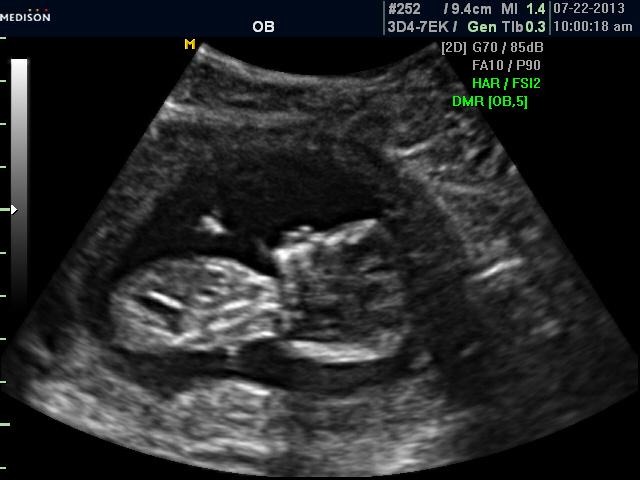

My little sister just had her u/s today..she is 13 weeks 6 days. Any guesses would be appreciated! Thank you all!Attachment 12505Attachment 12506Attachment 12507Attachment 12508

I *think* there is a boyish nub on the second picture. Only prob is that baby is pretty arched. I would go 60-40 boy.

Not sure there is a nub, but if what I am looking at is a hint of a nub I am thinking boy